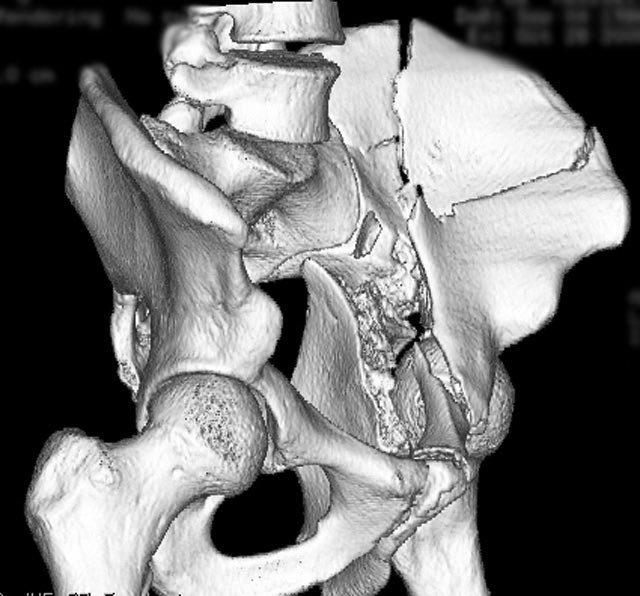

The surface rendered CT helps “to see” the AP plain film better

The iliac oblique SR image helps too

And the “spur” is identified when viewing it from this angle